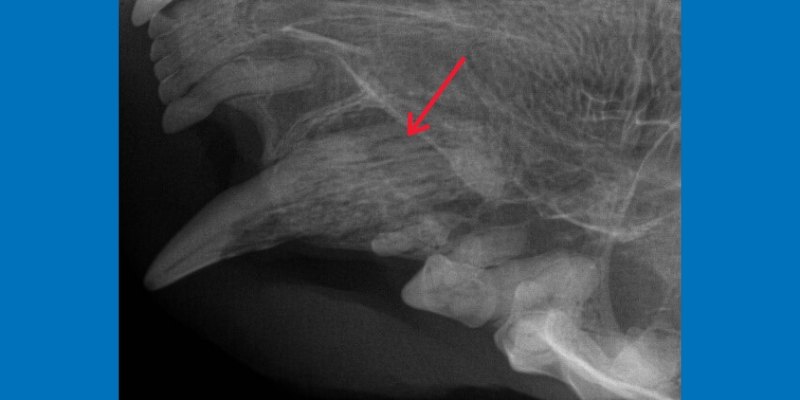

5. Tooth Resorption in Cats

Tooth resorption is a common condition in cats where the tooth structure erodes and can lead to painful lesions with the nerve tissue exposed. We need dental x-rays to assess the extent of the erosion and to decide on the appropriate type of treatment. A lot of times, tooth resorption is actually imperceptible until the x-ray is taken.

Maxillary canine tooth with tooth resorption in a cat (red arrow).